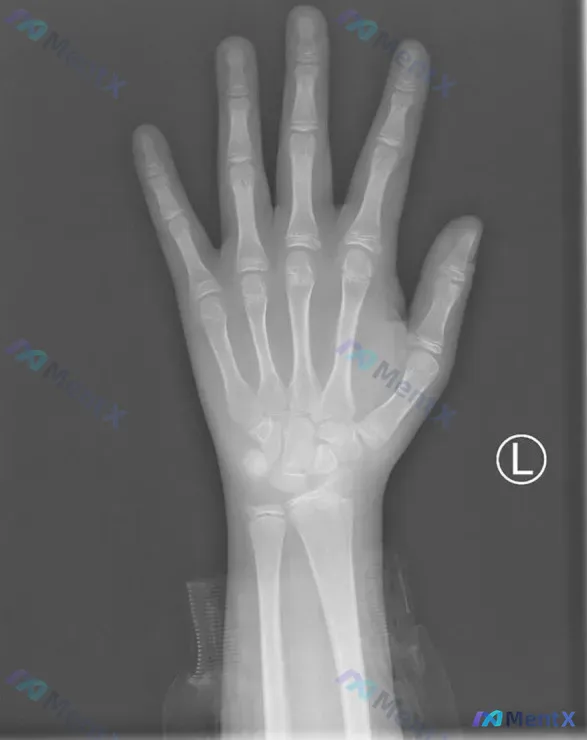

这是一张标记为L的左手正位X光片,投照体位基本符合标准,手指自然平展,掌骨、指骨及腕关节显示完整。

✅ 骨皮质:各指骨、掌骨、腕骨的骨皮质连续光整,未见中断、骨折线或骨痂

✅ 骨小梁:纹理清晰连续,分布均匀,无破坏、吸收或异常致密

✅ 关节结构:各掌指、指间、腕关节间隙宽度尚可,关节面光滑,对位对线良好,腕骨排列规则

✅ 骨骺状态:掌骨、指骨基底部及桡尺骨远端可见清晰透亮的骨骺软骨板

✅ 其他:无软组织肿胀、皮下气肿,无骨膜反应,无骨质疏松或硬化

结合现有信息,整体更倾向于这是一张未见明显异常的生长发育期骨骼影像——清晰的骨骺线是正常生理特征,不需要特殊干预。